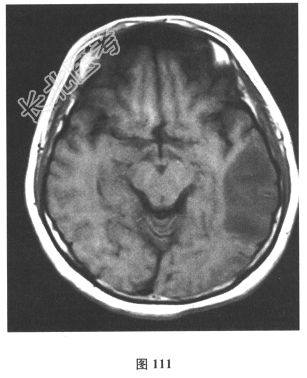

- 简答题2、脑脊液检查:常规、生化均正常,CSF-病毒TORCH(-),抗Hu、Yo、Ri均阴性,OB、MBP正常。血清抗Hu、Yo、Ri均阴性。颅脑MRI显示左颞枕、右顶枕多发长T₁、长T₂信号,Flair高信号,病变累及皮质及皮质下白质,病灶无强化,见图108~图114。)根据颅脑MRI,需要鉴别的疾病应是